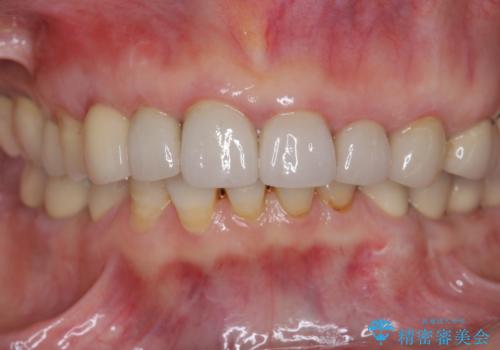

クラウン下に再発した深い虫歯 インプラントによる機能回復

前歯のインプラントを仕上げるには骨や歯ぐきの条件を整えることが肝要です。

- 45万円(ストローマンインプラント・骨造成・チタンカスタムアバットメント・ジルコニアクラウン)費用は治療当時の料金となります